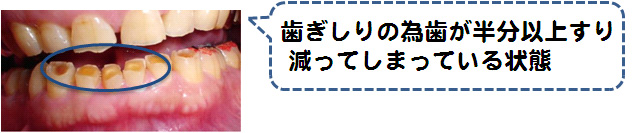

お口の中でも様々な諸症状が診られます!

※ 歯ぎしりだけではなく酸蝕症や様々な疾患を原因としてすり減る事もあります。